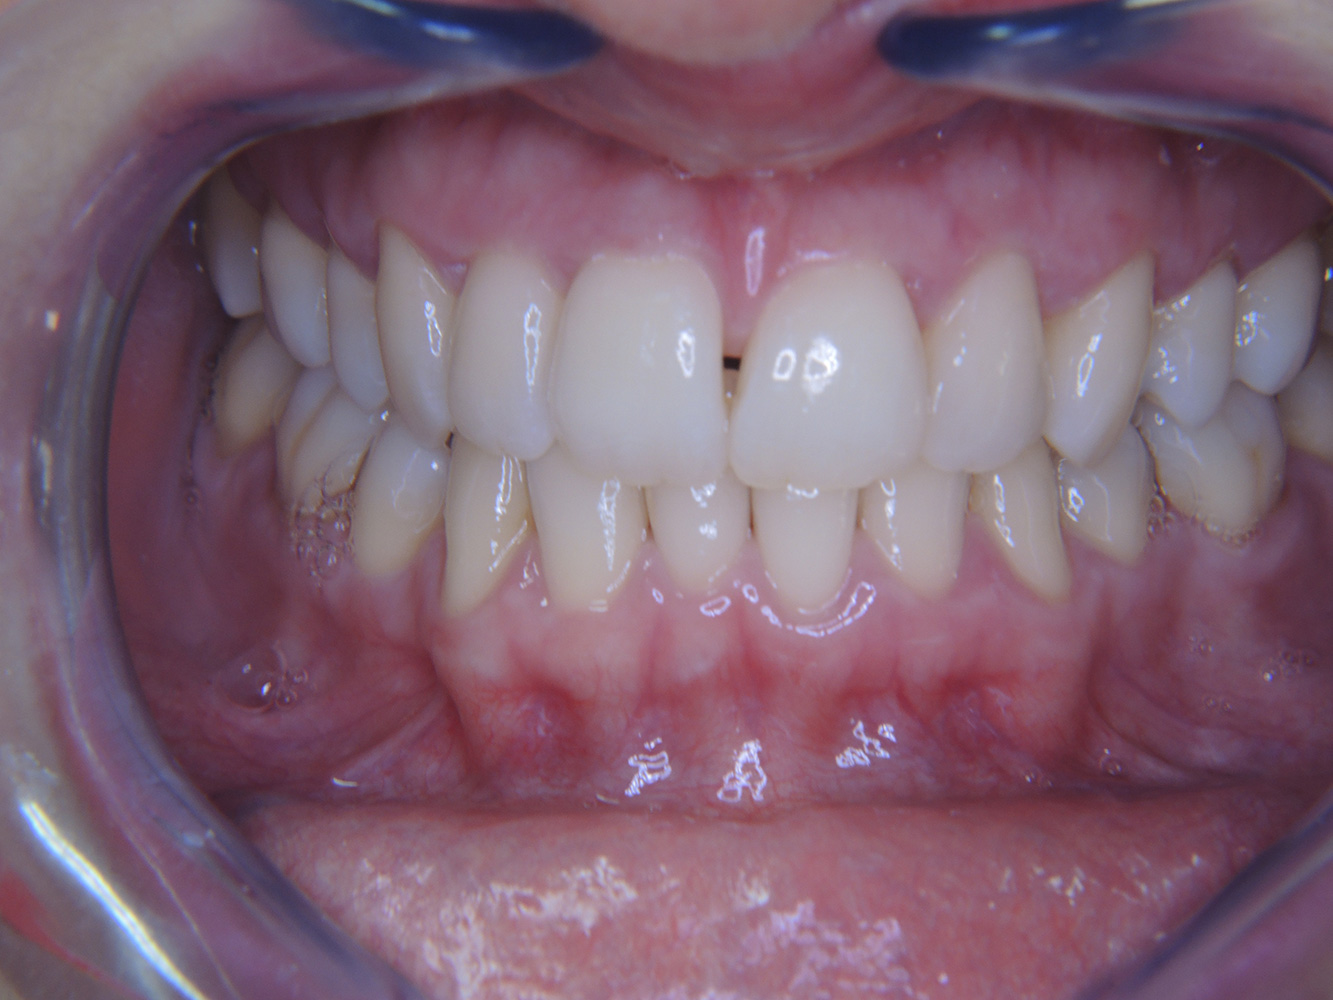

Următoarele studii de caz* acestea au rolul să ilustreze interacțiunea dintre necesitățile și factorii de risc definiți pentru IPC, precum și efectele factorilor individuali.

Fumător de 28 de ani cu eroziuni dentare

28-year-old patient, smoker, with erosions. The bidirectional relationship between oral and general medical health is very well known. It is no longer sufficient – and arguably even old-fashioned – to consider intraoral conditions in isolation. In order to create a personalized, case-specific preventive and patient profile, it is essential to take a detailed medical history and perform diligent examination of the general medical and intraoral health, as well as considering the two in combination. more